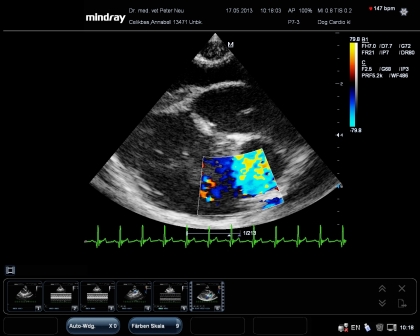

Eine besondere Herausforderung ist der Herzultraschall. Diese Untersuchung ist nur mit besonders leistungsfähigen Geräten mit speziellen Sonden möglich.

Hier ein Bild mit Farbdoppler. Es zeigt einen Schnitt durch die Herzbasis und dokumentiert Veränderungen an der Pulmonalklappe. So können dynamische Veränderungen im Herzen sichtbar gemacht werden. Gleichzeitig gibt es eine EKG Ableitung-